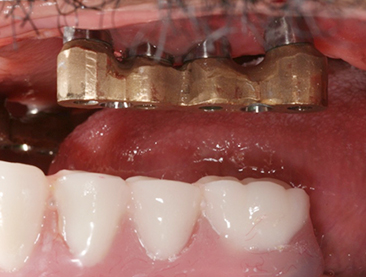

Implants/Bone Grafting

Fully edentulous clinical cases